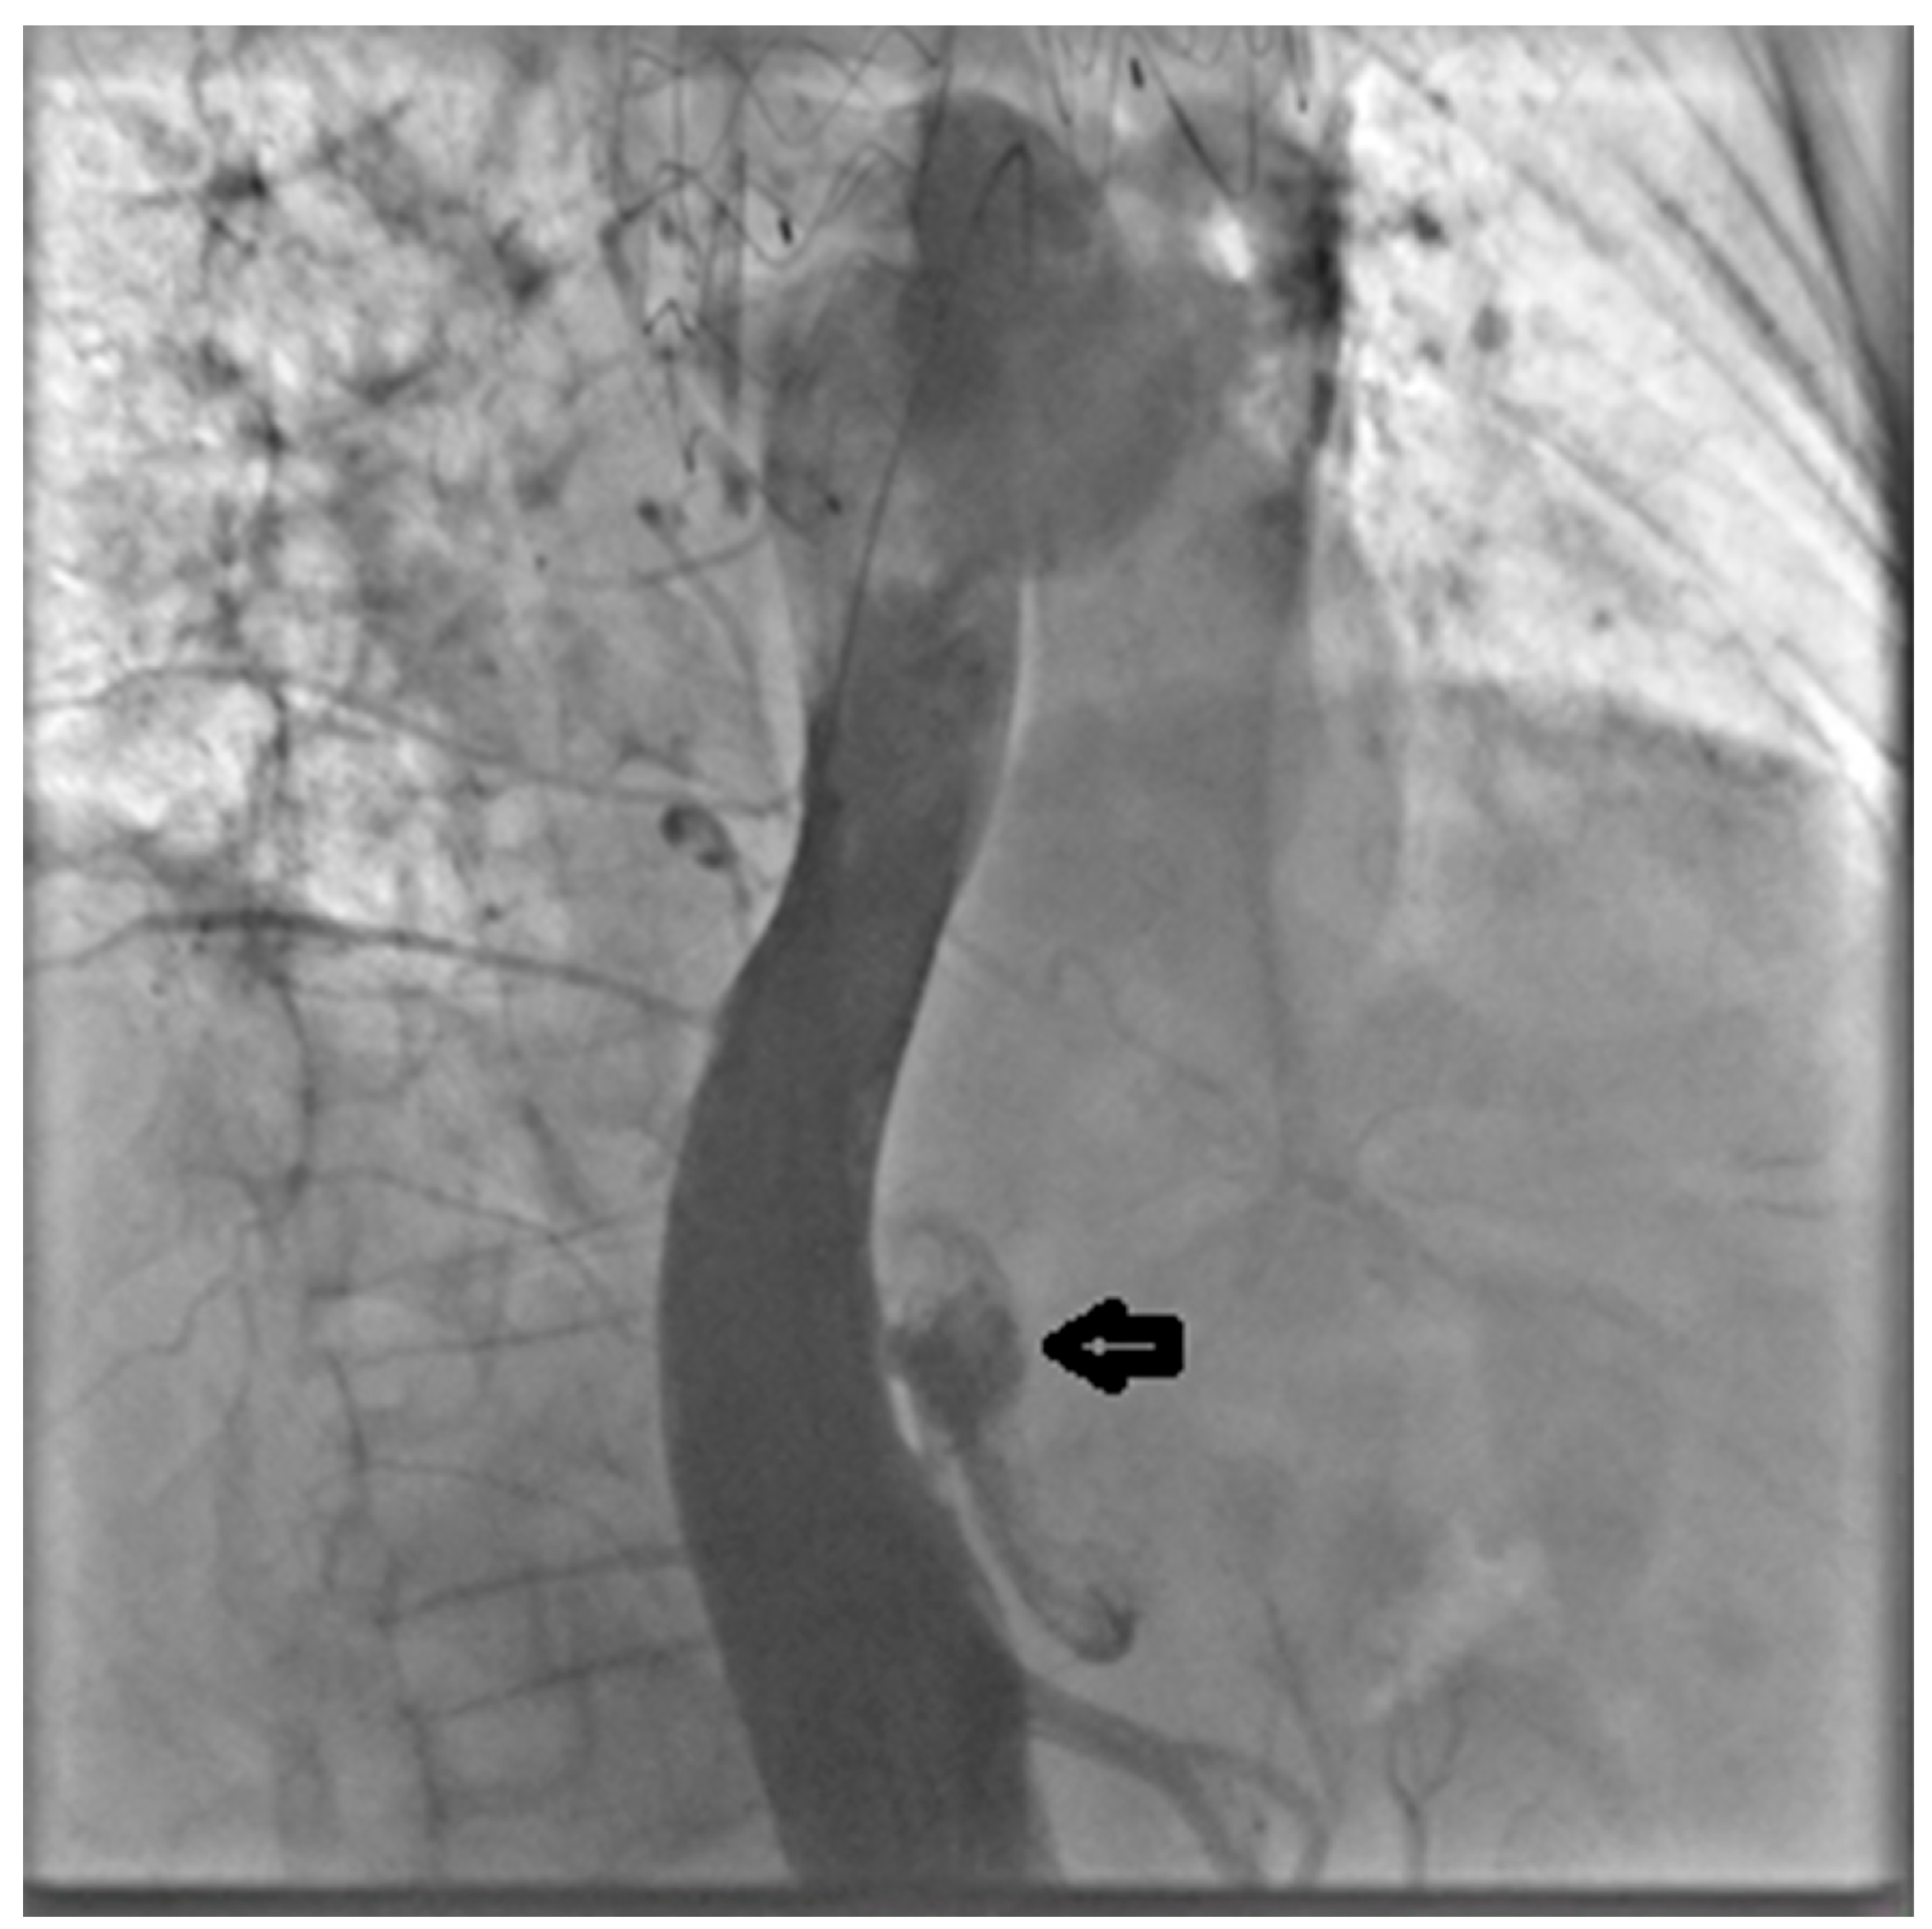

Through the LCFA, a 6F pigtail catheter was advanced into the thoracoabdominal aorta. Intraoperative angiography confirmed substantial FL dilation and two distal re-entry tears beyond the prior TEVAR, with clear retrograde backflow (Figure 2).

Figure 2. Intraoperative angiography with injection into the true lumen demonstrating marked false lumen dilation with evidence of a distal re-entry tear and retrograde backflow (arrow).